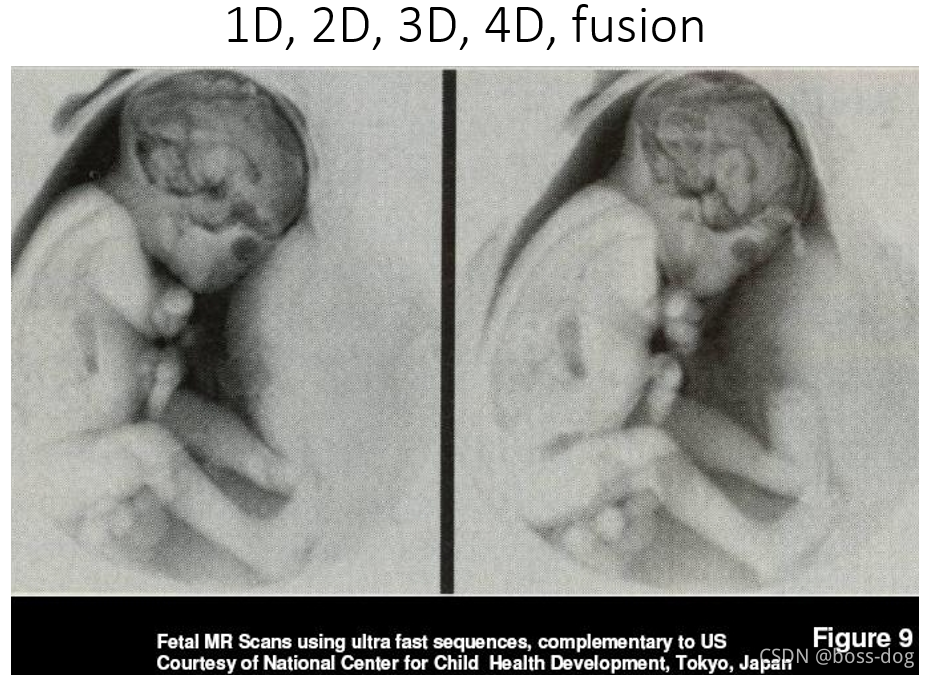

2.超声成像(UltraSound imaging)。没有那些辐射而且用的是声波,只不过频率要比声波要高,所以是安全的且特别方便,应用领域如解剖成像(Anatomical imaging)、多普勒超声(Doppler flow imaging,可以测量血管里面血流的速度和方向)、胎儿成像(Fetal Ultrasound)、心脏的超声成像(Echocardiography)。

一维1D:比如抽血中的各项数指标、血压的数值等等、二维2D:比如心电图采集的图片记录下来的信息、DICOM图片等等、三维3D和四维4D的涉及一些动态图片比如后处理很酷炫的图片或分割的结果等等